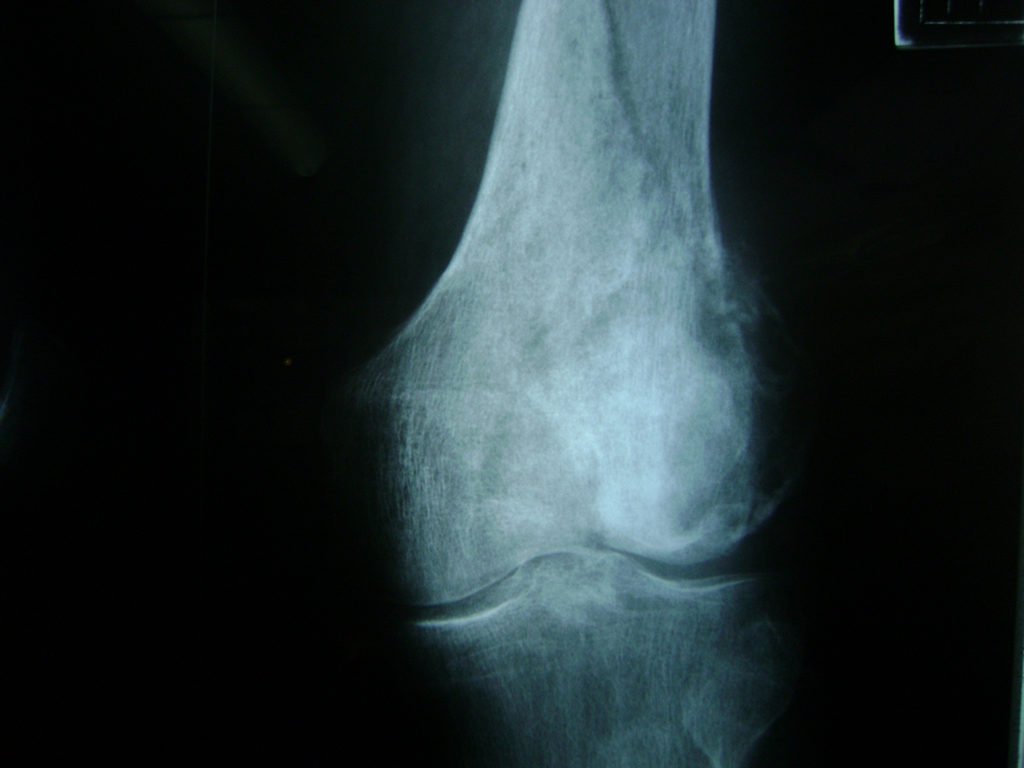

Fémur - Rodilla

La artroscopia de rodilla es un cirugía en el cual la estructura interna de la articulación es examinada ya sea para realizar un diagnostico o para realizar un tratamiento, este procedimiento se realiza utilizando un instrumento parecido a un pequeño tubo llamado artroscopio.